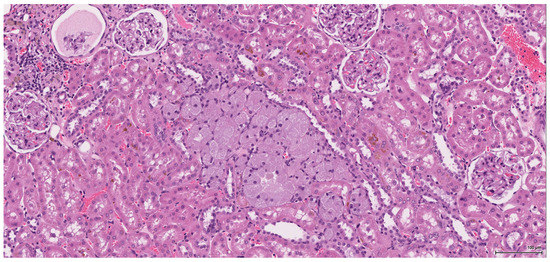

The renal lesional background is represented in most cases by different stages of chronic progressive nephropathy including degenerative and regenerative aspects: vacuolar cytoplasmic degeneration; cortical subcapsular foci of small basophilic tubuli, some of them with thickened basement membrane; compensatory enlarged hypertrophic tubuli; cystically dilated tubuli or glomeruli with glomerular metaplasia of the parietal Bowman’s capsule (typically appears in rat females after administration of androgenic compounds); casts, both hyaline and granular; variably sized cysts located within the medulla and lined by an attenuated epithelium (toxic effect or ageing related). Along with these features, regenerative tubule hyperplasia and even oncocytic hyperplasia (Figure 11) were identified in two cases. Extensive tubule necrosis is seen in one case and moderate chronic inflammatory infiltrate in another; minimal papillary urothelial hyperplasia is associated in one case.

Figure 11. H&E: Female NTP non-tumour case: oncocytic hyperplasia (centre) with enlarged, finely granular, pale eosinophilic cytoplasm.